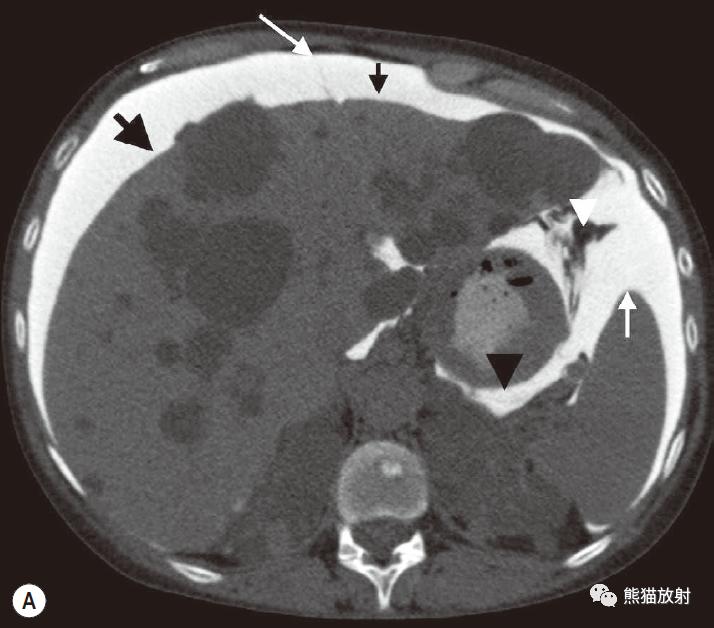

腹水的CT值范围从0~30HU,是非特异性的,随蛋白质含量的增加而增加,出血时密度较高。

漏出液:可能与门静脉高压、肝硬化、心脏功能不全、肾病综合征或下腔静脉、肝静脉、门静脉阻塞相关。可以再腹膜腔内弥漫而没有显著的腹膜反应。

渗出液:可能与感染或腹膜转移相关。不能在腹膜腔内自由移动,而通常位于或被隔离在其来源区域。

积血:可能由创伤、出血性体质或肿瘤破裂引起。